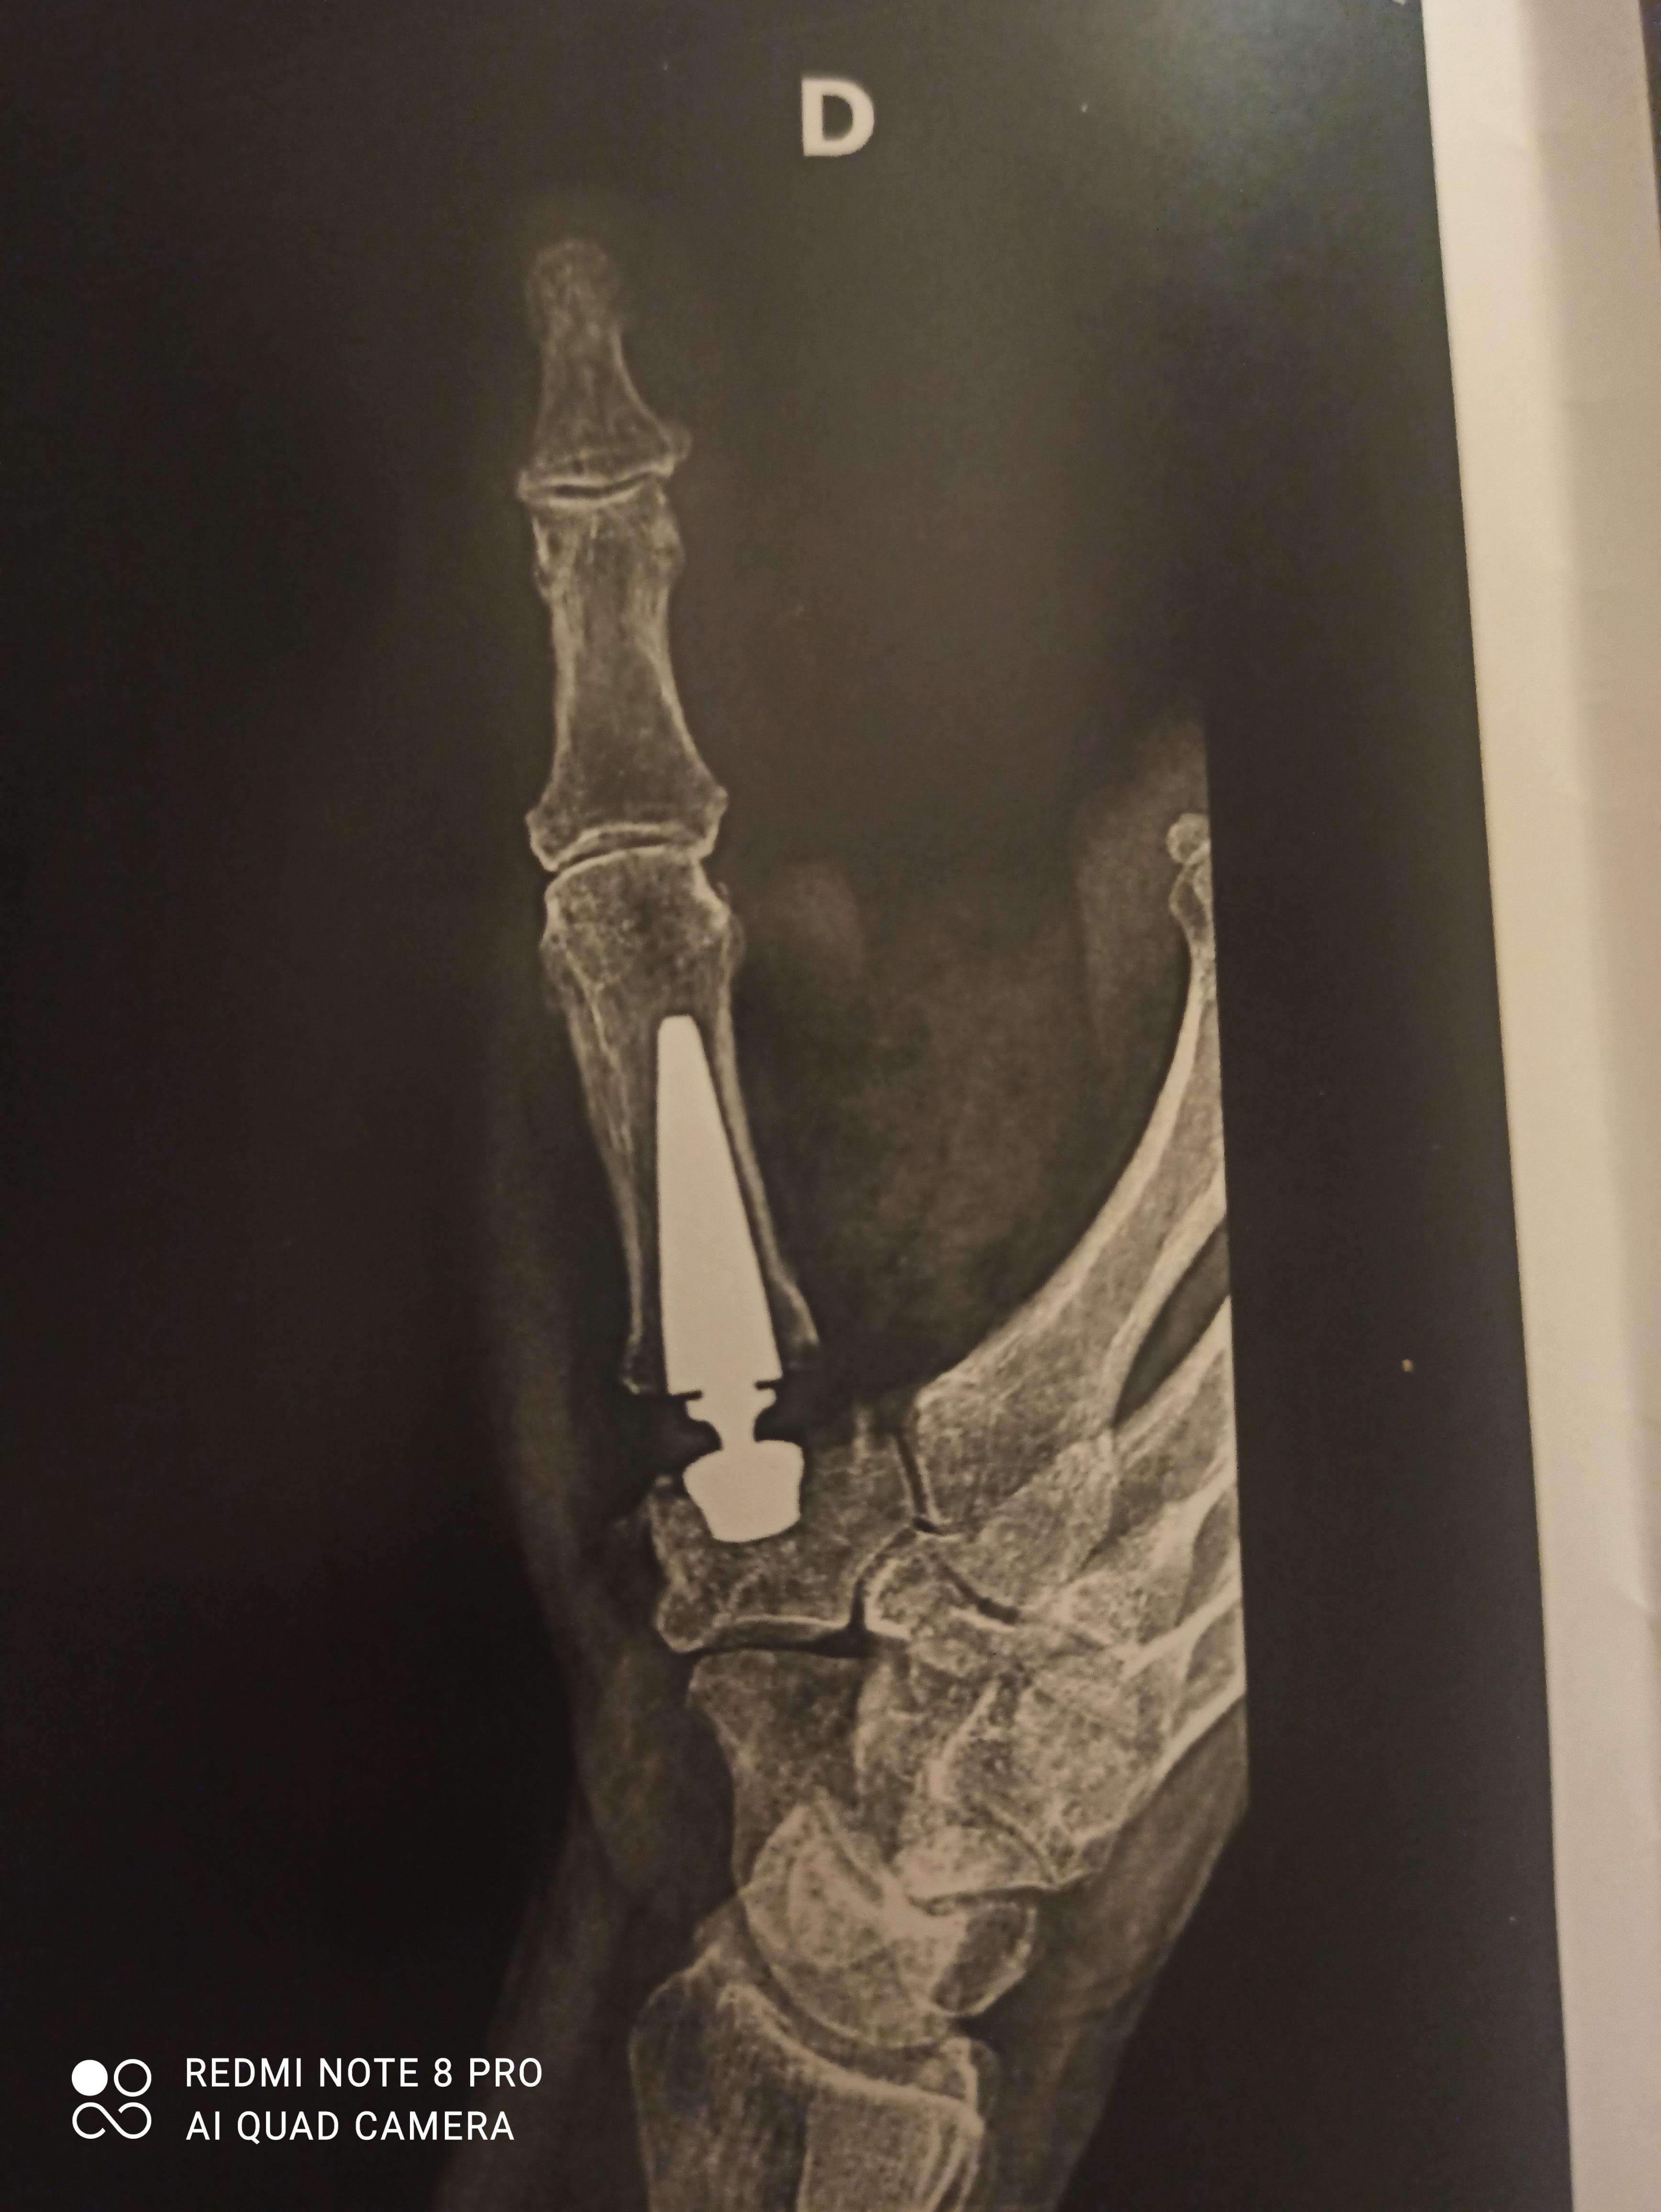

Un grand merci au Dr Winter et son équipe, un chirurgien au top, avec des explications très claires concernant la pose de ma prothèse de pouce, moi qui était terrorisée de me faire opérer, car je suis coiffeuse et j'ai besoin de mes mains pour exercer ma profession, il a su m'écouter et me rassurer , résultat : un travail très propre 👍 photos ci-jointes , je le recommande à 100%, n'hésitez vraiment pas à le consulter 🙏